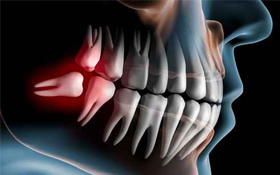

親知らず

親知らずとは、前の歯から数えて8番目に位置する奥歯のことを言います。他の歯とは違い、生えてくるのが20歳前後と遅いことが特徴です。最大で上下左右の奥に4本生えます。昔の人は顔が大きく顎も広かったため、親知らずが生えてもそれほど問題はなかったのですが、現代日本人は顔が小さくなり顎も狭くなっているため、生えてきた際に何かと問題が起きてしまいます。

親知らずを抜かなければいけない理由

- 衛生的な問題

- 歯並び、噛み合わせの問題

生え方によっては、その歯、また隣接する歯が磨きづらくなり、ケアが不十分になってしまいます。結果として虫歯や歯周病になってしまうのを防ぐために前もって抜いておく必要があります。

水平方向に生えた場合など、正常な他の歯を動かすことになり、噛み合わせに異常をきたすことになってしまいます。それを防ぐために抜歯する必要があります。

親知らずは放置しても問題ないものもあります。しかし、自分の親知らずに問題があるのかないのか、それをご自身で判断することはなかなか難しいです。

問題のない親知らずならば良いのですが、問題がある親知らずの場合、以下のような弊害が起こる恐れがあります。

- 噛み合わせ異常によって頭痛や肩こりが起こる。

- ケアが不十分になり口臭が発生する。

- 歯並びが悪くなる。

- 細菌感染してしまい、腫れが親知らず周辺から、顎の下、喉周辺、そして最悪心臓部まで広がってしまう。心臓に達した場合は、最悪死亡するというケースもあります。

「歯を抜くのが怖いから」などという理由で放置などしたりせず、早い段階から医師に相談して、最善の選択が出来るようにすることをおすすめいたします。